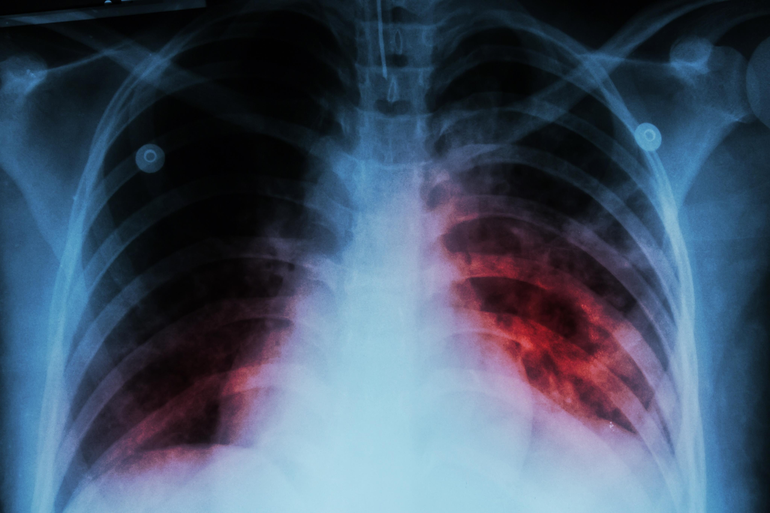

"Las personas que están dos o tres semanas con tos permanente, que levantan fiebre, que han perdido peso, que por las noches sudan al punto de mojar ropa o sábanas, ahí uno puede sospechar como personal de salud que tiene Tuberculosis y realizarle, entonces, radiografía y otros estudios para confirmarlo", indicó.

Es una enfermedad bacteriana que generalmente ataca los pulmones. Pero también puede afectar otras partes del cuerpo, incluyendo riñones, la columna vertebral y el cerebro. No todas las personas infectadas con la bacteria de la tuberculosis se enferman.